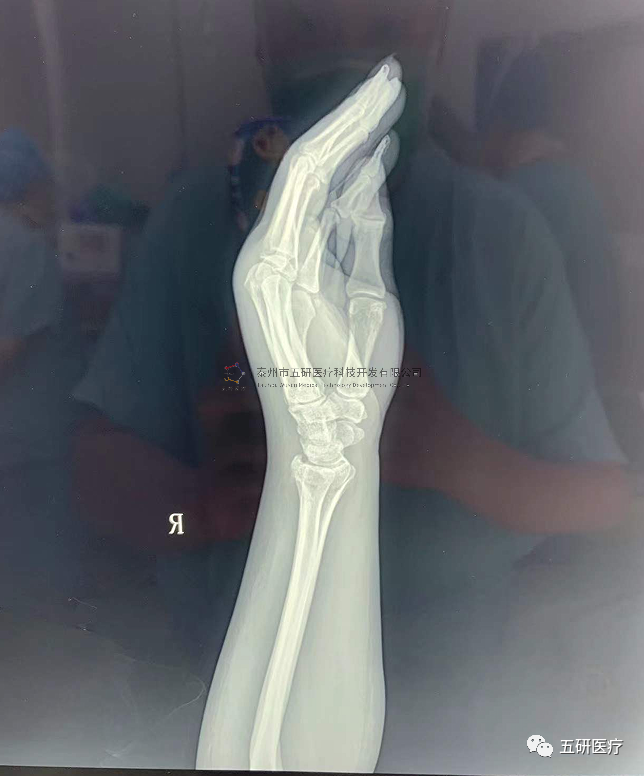

3.png

2

// 踝關(guān)節(jié)

本病例由中國(guó)中醫(yī)科學(xué)院望京醫(yī)院骨關(guān)二提供(術(shù)者:支架主任蔣主任)

【基本資料】患者,男,41歲

本病例踝關(guān)節(jié)骨折。手術(shù)名稱:左踝關(guān)節(jié)骨折外固定支架手術(shù)